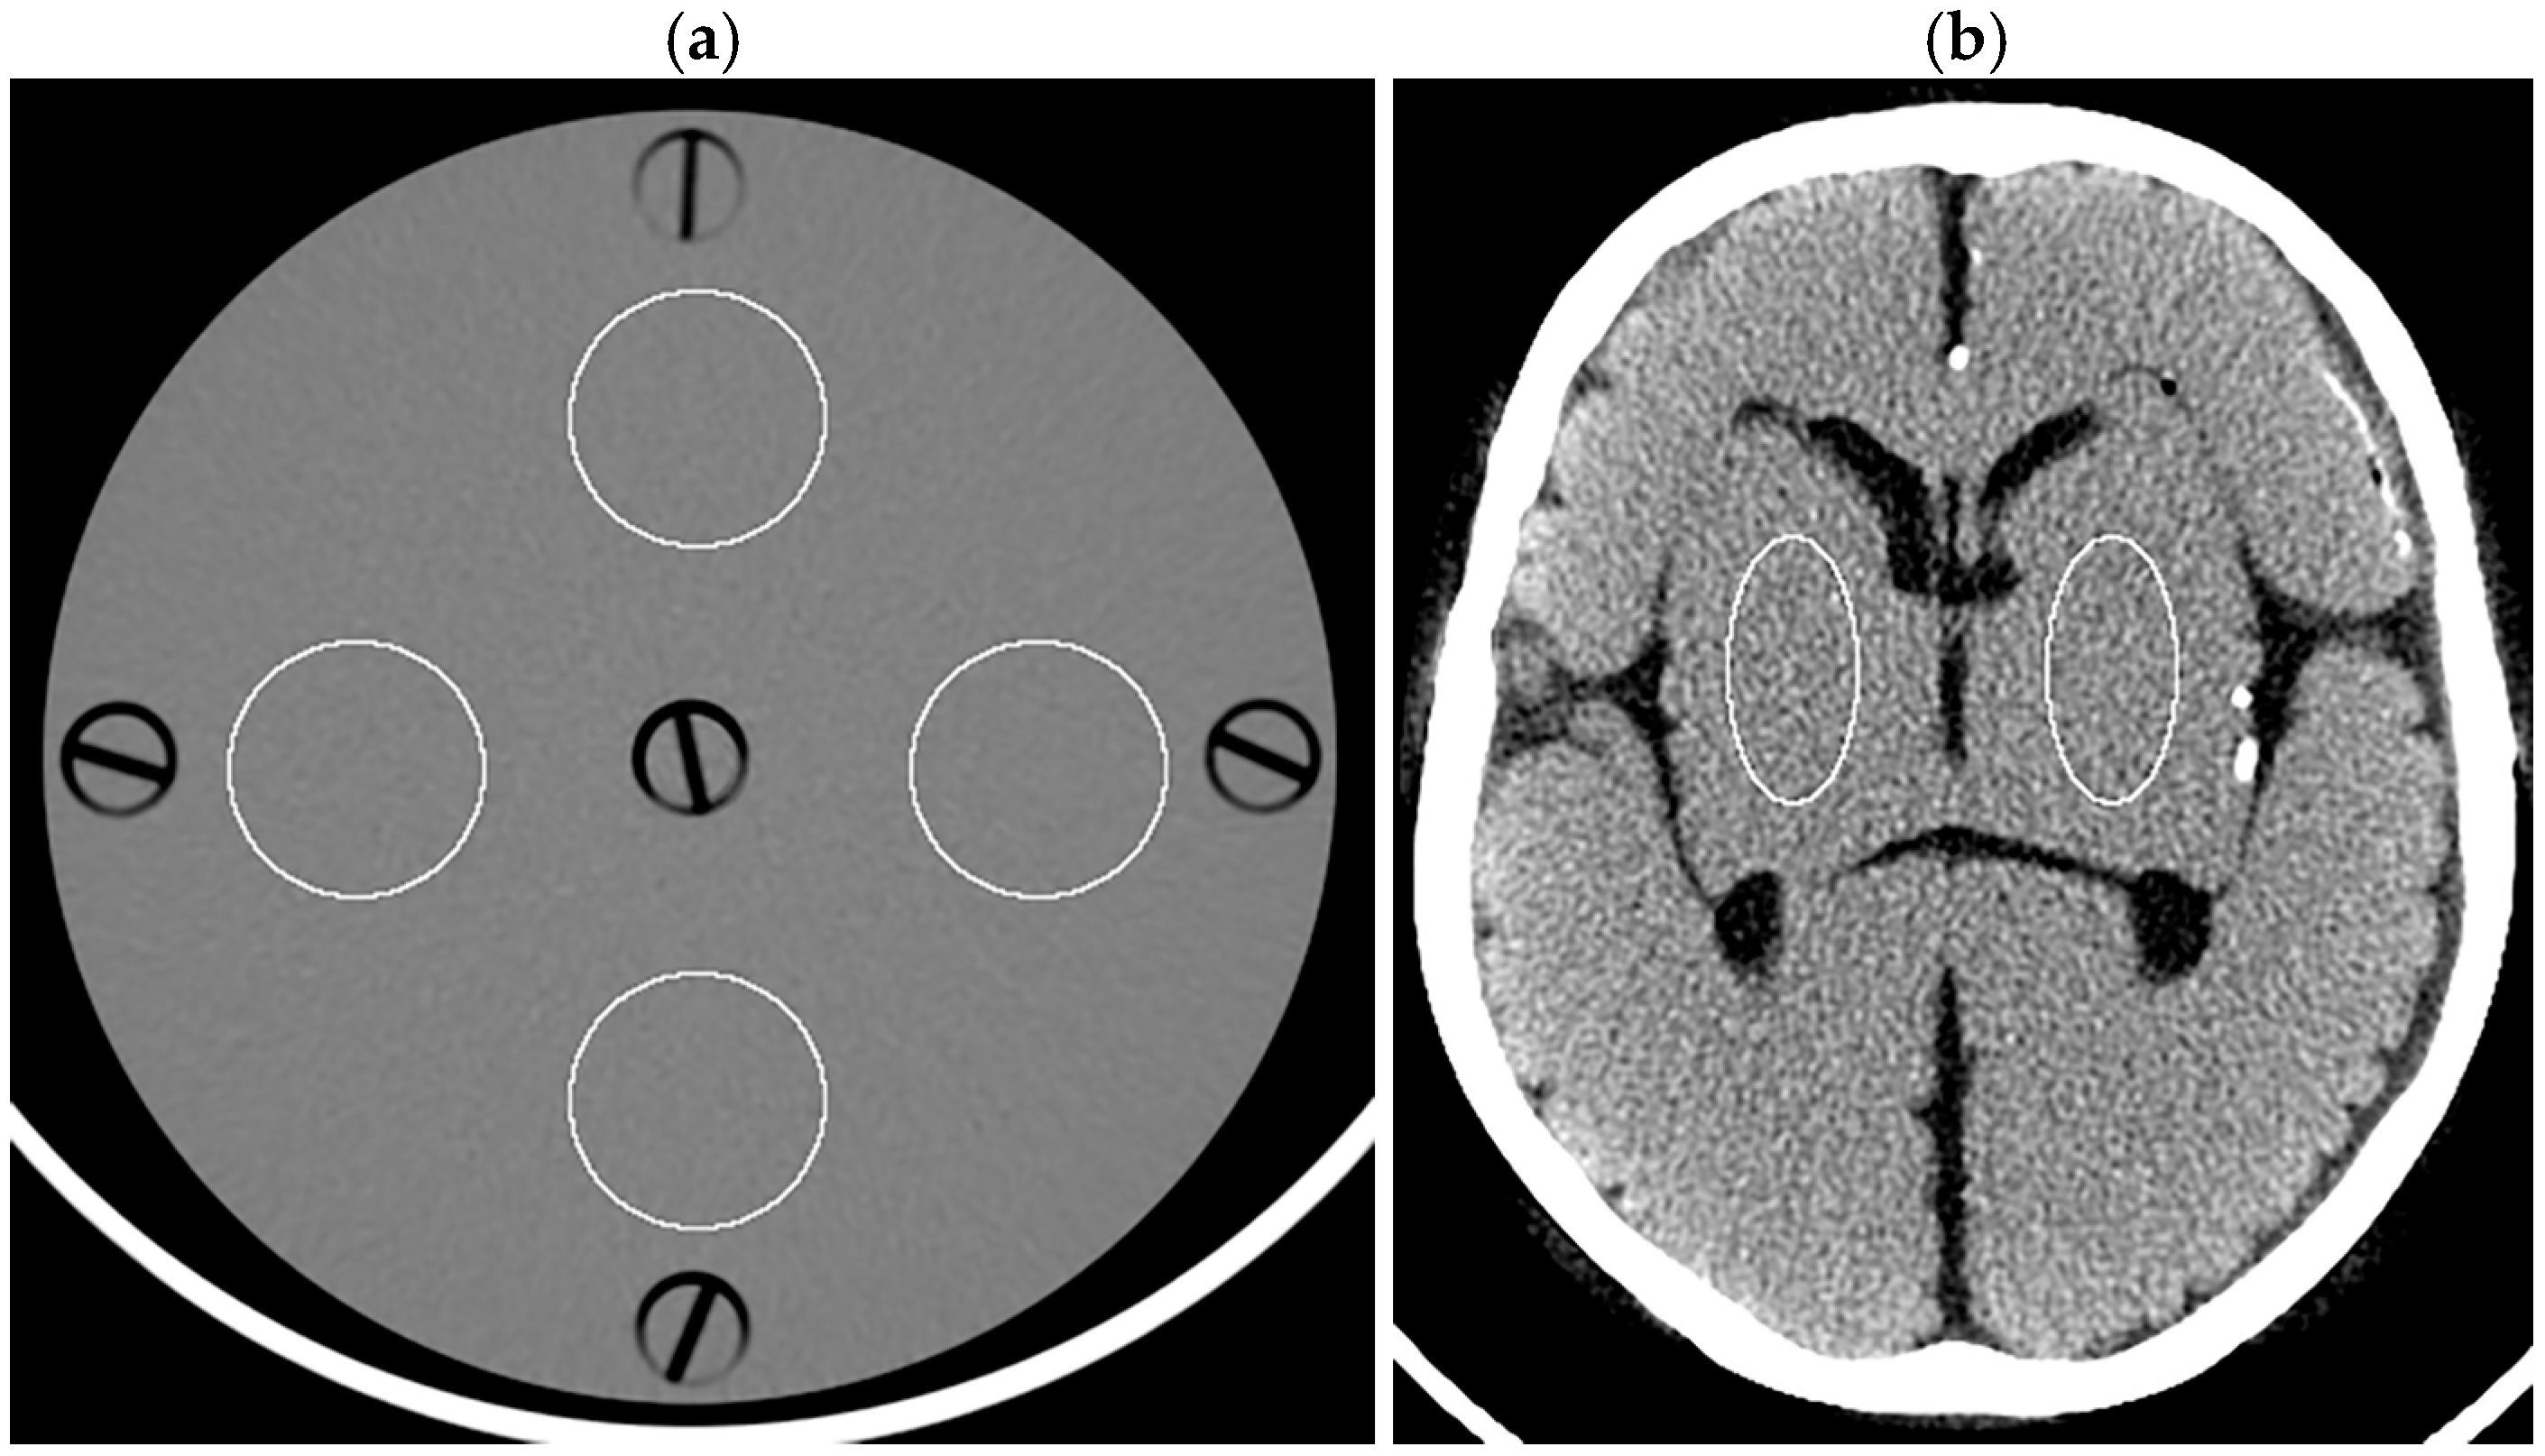

In analyzing the dosimetry phantom images, four circular regions of interest (ROIs, 766.6 mm2 each) were placed on a 5 mm thick image reconstructed with FBP and then applied to other images using ImageJ software (version 1.54g; National Institutes of Health, Bethesda, MD, USA) (Figure 1a). The SD of the Hounsfield unit was obtained for each ROI, and the mean SD across the four ROIs was defined as the image noise. For the head phantom, elliptical ROIs (527.4 mm2 each) representing the right and left lenticular nuclei were placed (Figure 1b). The SD was obtained for each ROI, and the right and left values were averaged to determine the image noise. Noise reduction ratios for various levels of DLR and HIR were calculated using the image noise for the FBP image of the corresponding thickness as the reference as follows:

Figure 1.

ROIs displayed on the 5 mm thick FBP images of the dosimetry phantom (a) and head phantom (b).